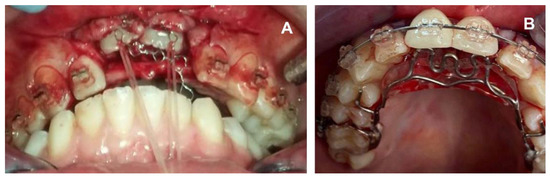

2. Case Report

2.1. Clinical History

2.2. Clinical Exams and Diagnosis

2.3. Therapeutic Plan

3. Results